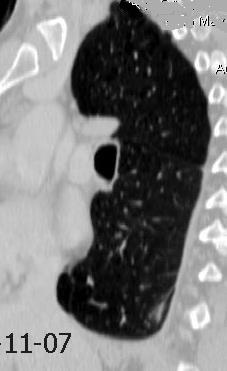

87. NEUMOTÓRAX ESPONTÁNEO

89. NEUMOTÓRAX. SÍNDROMES POROSOS

90. NEUMOTÓRAX A TENSIÓN

91. NEUMOTÓRAX EN ESPIRACIÓN

92. PLACAS PLEURALES

94. QUILOTÓRAX